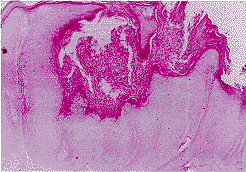

1.1 组织标本 病例选自我院1990~1998年资料完整的KA共20例,男14例,女6例,年龄48~83岁,平均68岁。病程1~30月,平均8月。单发型14例,多发型(2个以上)6例。按文献〔2〕方法作组织学分期:增生期6例,成熟期12例,消退期2例(图1~3)。均发生在头面和手背等暴露部位。全部病例取活检前均未接受过特殊治疗。病理切片均经皮肤病理医师再次确诊。石蜡包埋组织标本,行3 μm厚连续切片,1张常规HE染色,2张TUNEL法染色,4张作免疫组化研究。

图1 增生期角化棘皮瘤.HE×25

图2 成熟期角化棘皮瘤.HE×30

图3 消退期角化棘皮瘤.HE×100